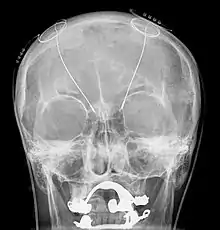

Estimulação cerebral profunda ou ECP (do inglês Deep Brain Stimulation (DBS)) é um tratamento neurocirúrgico para transtornos neurológicos usando um marcapasso cerebral que envia impulsos elétricos a determinada parte do encéfalo. É usado no tratamento de doenças neurológicas em que a medicação não foi eficiente e que causa amplos prejuízos ao paciente.[1]

Com a instalação cirúrgica de eletrodos no cérebro, um controle externo permite regular a estimulação elétrica da áreas subcorticais com déficit neurológico e assim reequilibrar os circuitos neuronais danificados diminuindo a frequência de problemas como tremores, rigidez e contrações musculares involuntárias. Mesmo sem medicação complementar diminui aproximadamente 57% desses sintomas.[12]